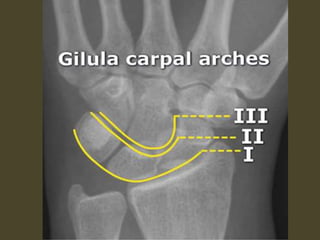

Wrist X-ray Anatomy.